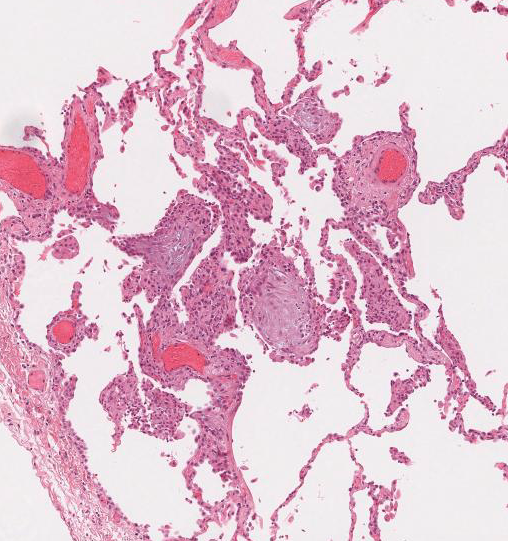

Normal lung

Emphysema, small areas of pneumonia in base